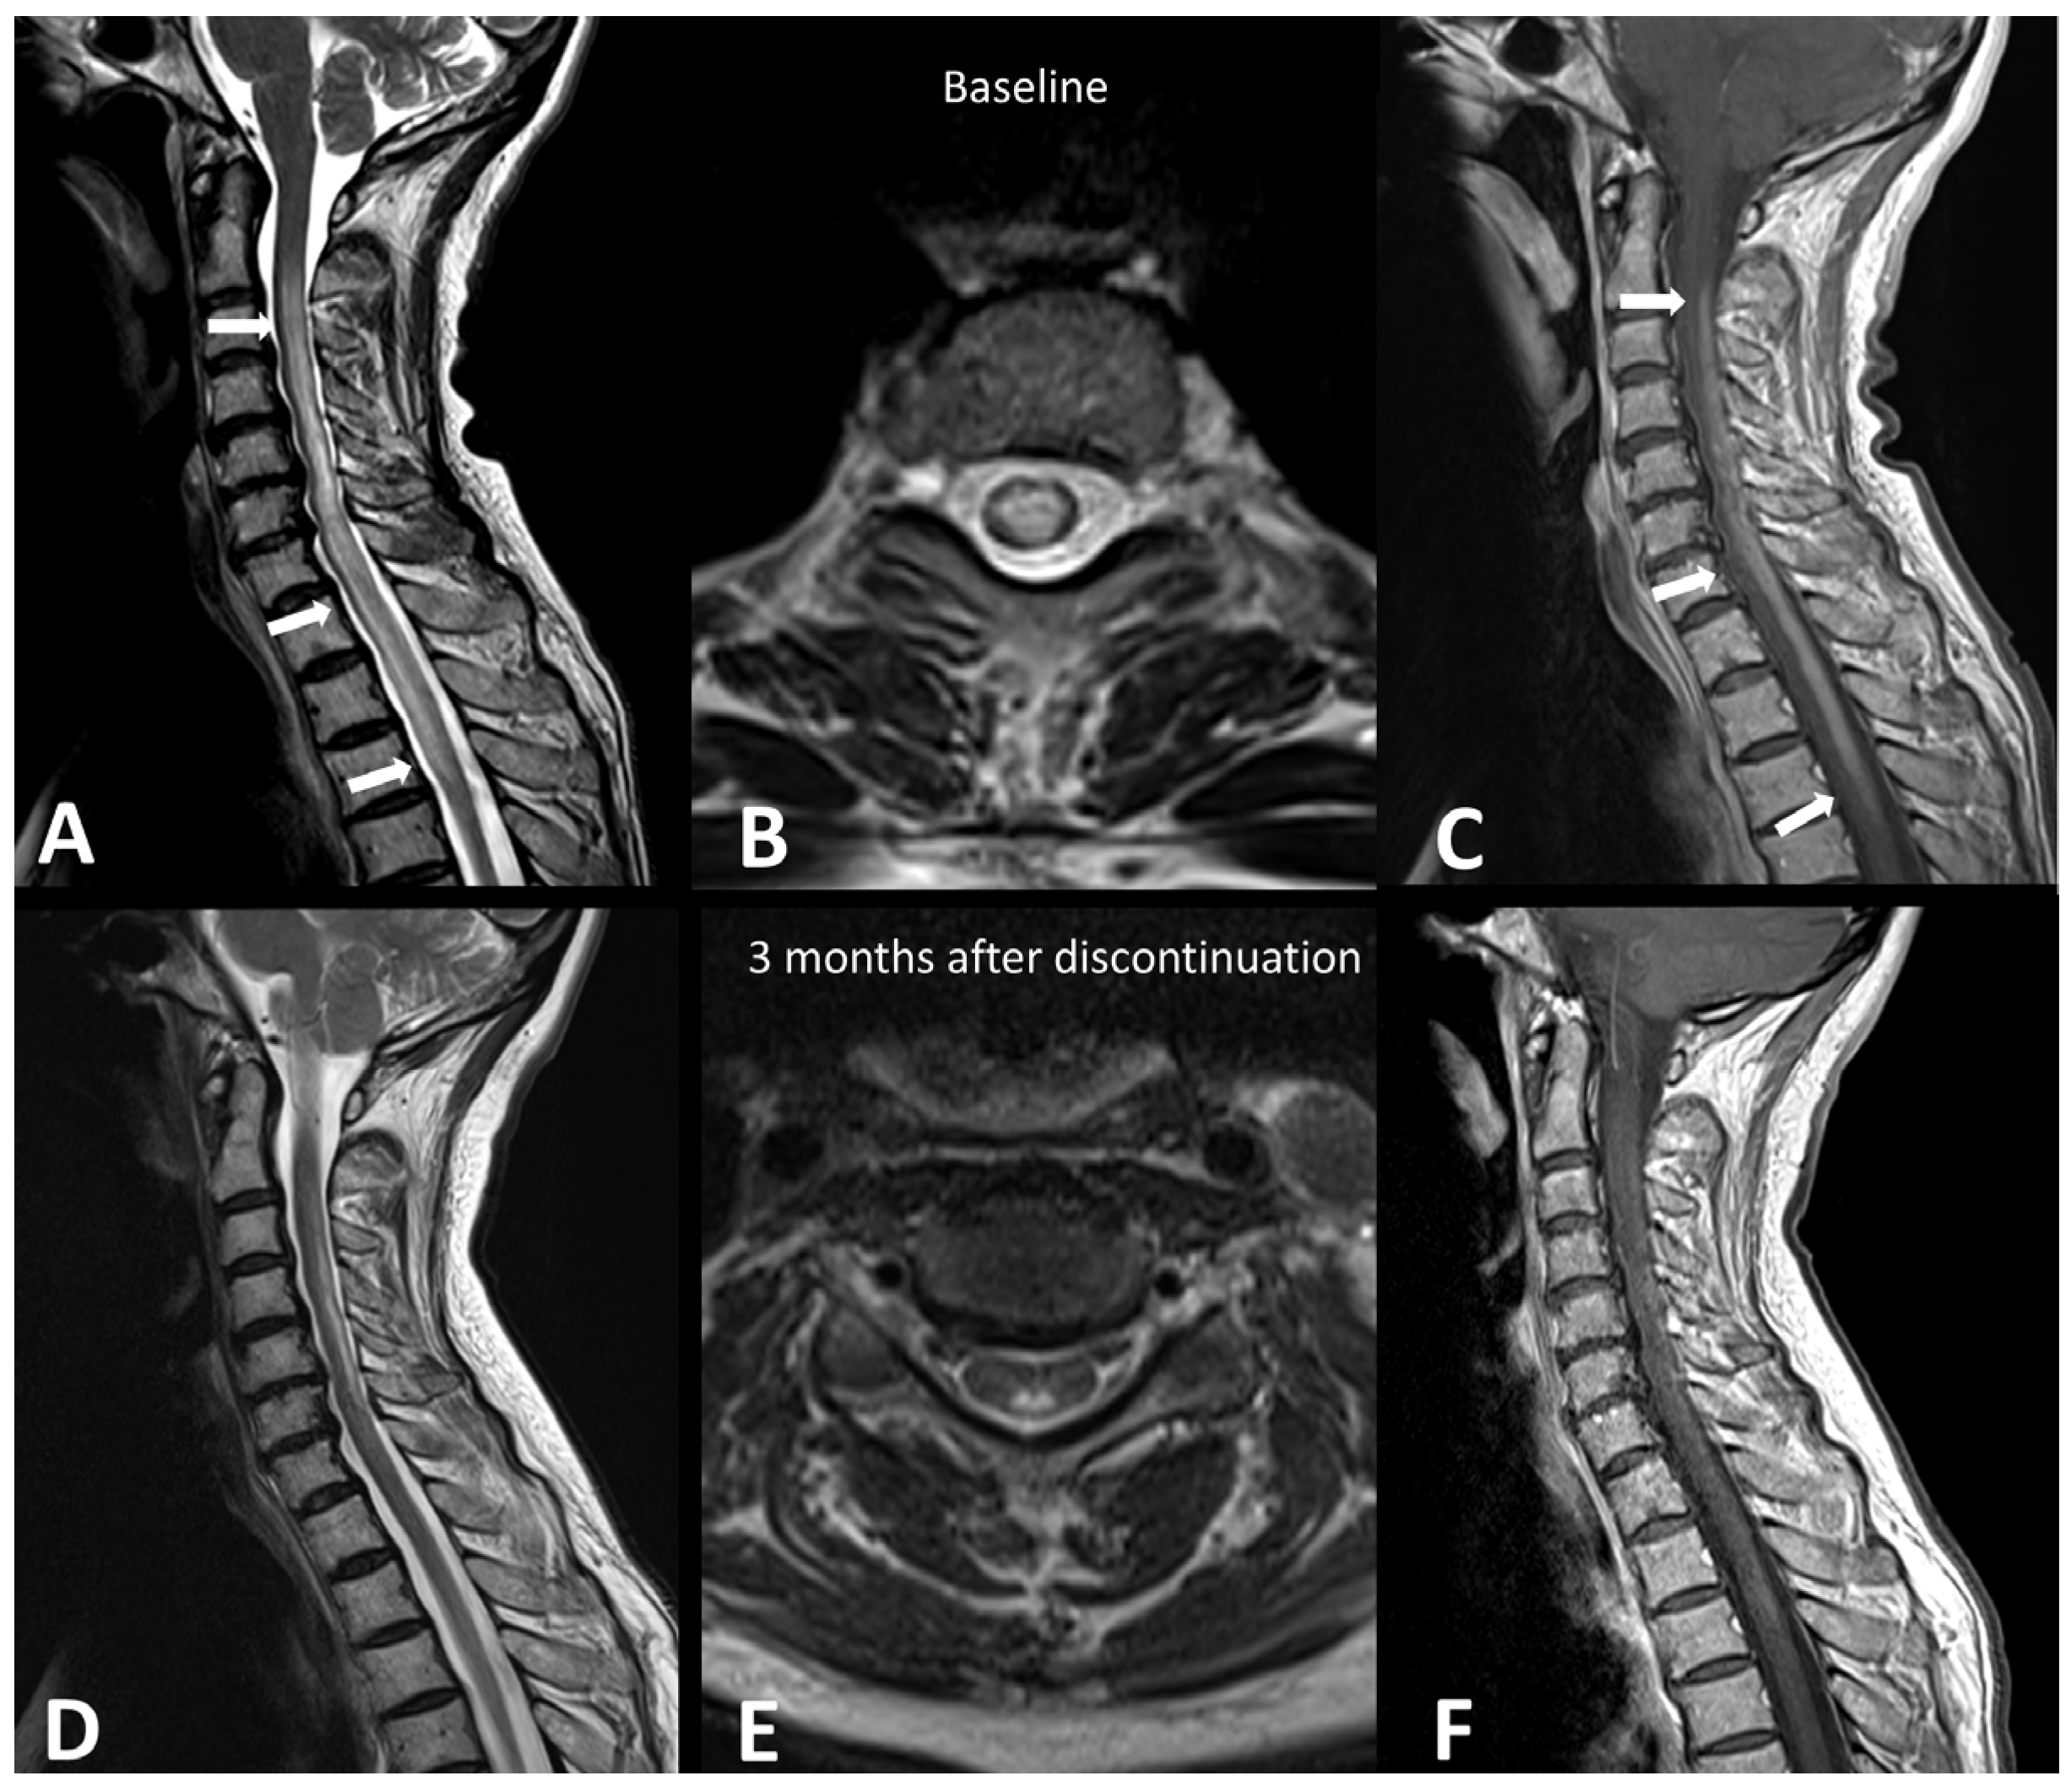

2.1.4. Ir-Demyelinating Disease and Myelitis

- Picca, A.; Berzero, G.; Bihan, K.; Jachiet, V.; Januel, E.; Coustans, M.; Cauquil, C.; Perrin, J.; Berlanga, P.; Kramkimel, N.; et al. Longitudinally Extensive Myelitis Associated with Immune Checkpoint Inhibitors. Neurol. Neuroimmunol. Neuroinflammation 2021, 8, e967. [Google Scholar] [CrossRef]

| Transverse myelitis | CE spine MRI + LP + autoantibodies | multiple sclerosis, neuromyelitis optica spectrum disorder, infectious myelitis | T2 hyperintensities > vertebrae, patchy contrast enhancement | |